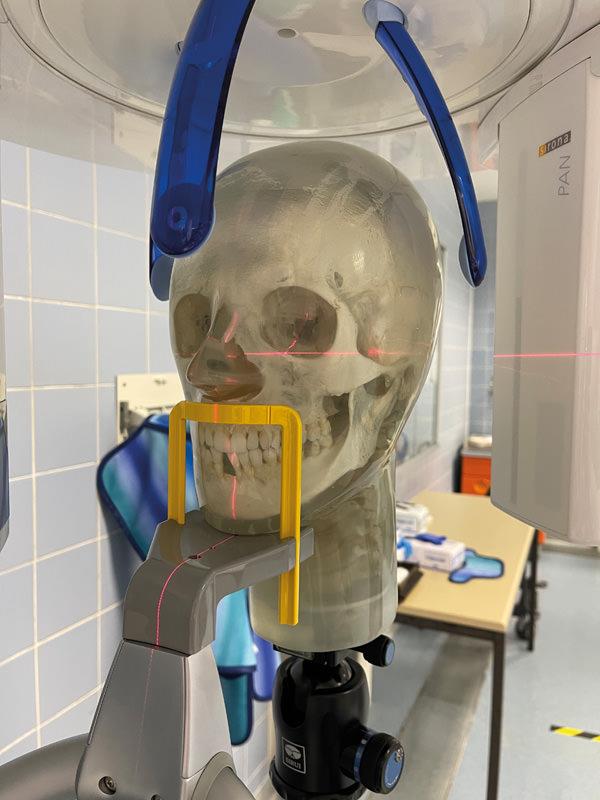

Menschlicher Schädel, sicher eingebettet in Kunststoff für einfache Handhabung. Der Kiefer ist leicht geöffnet, so dass die Zähne gut für Panoramaaufnahmen im Dentalbereich geeignet sind. Der Hals verfügt über Halswirbel. Ein eingebettetes Gewinde ermöglicht die Befestigung eines Stativs.